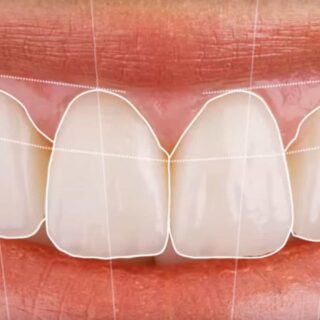

¿CUÁNDO ES MEJOR UNA INCRUSTACIÓN DENTAL QUE UN EMPASTE?

Cuando un diente sufre una caries extensa o una fractura, una de las dudas más frecuentes en consulta es si basta con un empaste o si conviene una solución más...